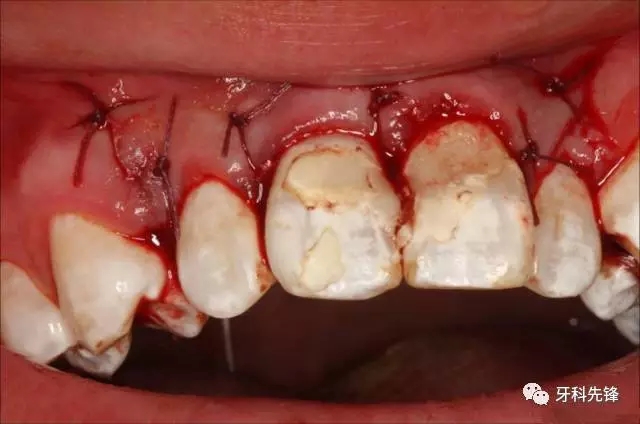

圖13.縫合

圖14.縫合完畢的口內照片